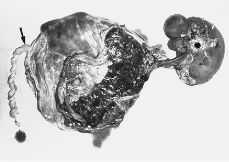

La radiología del feto acardio mostró una columna vertebral con algunos arcos costales sin objetivarse otro tipo de estructuras óseas (Fig. 5).

Figura 5. Radiografía del feto acardio que muestra una columna vertebral con algunos arcos costales.

La necropsia del feto acardio informaba de la presencia de un mamelón cefálico de 5 cm de diámetro mayor y dos pequeños mamelomes braquiales. La región dorsal estaba revestida parcialmente de piel y pelo y en la zona media central se observaba la presencia del cordón umbilical. En el interior de la masa existía una zona central ósea que parecía corresponder a la columna vertebral. La microscopía informa de tejidos infartados en los que sólo se identificaba piel, anejos cutáneos, estructuras vasculares, tejido adiposo, músculo estriado, hueso y cartilago.